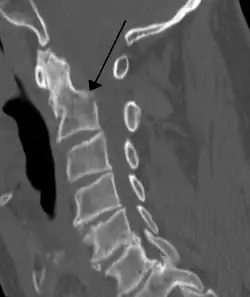

A fracture of the base of the dens as seen on CT -

Fractures of the dens are classified into three categories according to the Anderson Alonso system:

- Type I fracture - Extends through the tip of the dens. This type is usually stable.

- Type II fracture - Extends through the base of the dens. It is the most commonly encountered fracture for this region of the axis. This type is unstable and has a high rate of non-union.

- Type III fracture - Extends through the vertebral body of the axis. This type can be stable or unstable and may require surgery.[1]